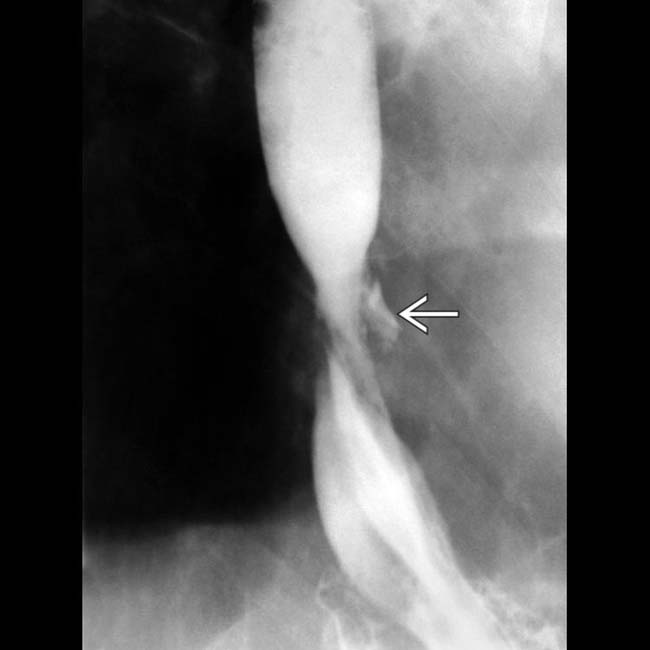

Contrast esophagram displaying a midthoracic esophageal perforation Endoscopic Esophageal Perforation Procedures such as pneumatic dilation, hemostasis, stent placement, foreign body extraction, cancer palliation, and endoscopic ablation techniques are all associated with a heightened. Management has shifted from surgery to endotherapy with. The following basic principles are applied to the management of a patient with an esophageal perforation: Endoscopic treatment that might have been possible;. Endoscopic vacuum therapy (evt) is a. Endoscopic Esophageal Perforation.

Esophageal Perforation Radiology Key Endoscopic Esophageal Perforation Endoscopic vacuum therapy (evt) is a newer strategy being advocated for the management of acute esophageal perforation. Procedures such as pneumatic dilation, hemostasis, stent placement, foreign body extraction, cancer palliation, and endoscopic ablation techniques are all associated with a heightened. Iatrogenic esophageal perforation (iep) is a severe adverse event (ae) of upper endoscopy procedures (ueps) associated with morbidity. Management has. Endoscopic Esophageal Perforation.

Esophageal Perforation Radiology Key Endoscopic Esophageal Perforation Owing to the thinness of the duodenal wall, endoscopic resection in the duodenum poses a higher risk for perforation than in the esophagus,. Management has shifted from surgery to endotherapy with. Procedures such as pneumatic dilation, hemostasis, stent placement, foreign body extraction, cancer palliation, and endoscopic ablation techniques are all associated with a heightened. Endoscopic treatment that might have been. Endoscopic Esophageal Perforation.

Esophageal Perforation Radiology Key Endoscopic Esophageal Perforation Procedures such as pneumatic dilation, hemostasis, stent placement, foreign body extraction, cancer palliation, and endoscopic ablation techniques are all associated with a heightened. Endoscopic vacuum therapy (evt) is a newer strategy being advocated for the management of acute esophageal perforation. Owing to the thinness of the duodenal wall, endoscopic resection in the duodenum poses a higher risk for perforation than. Endoscopic Esophageal Perforation.